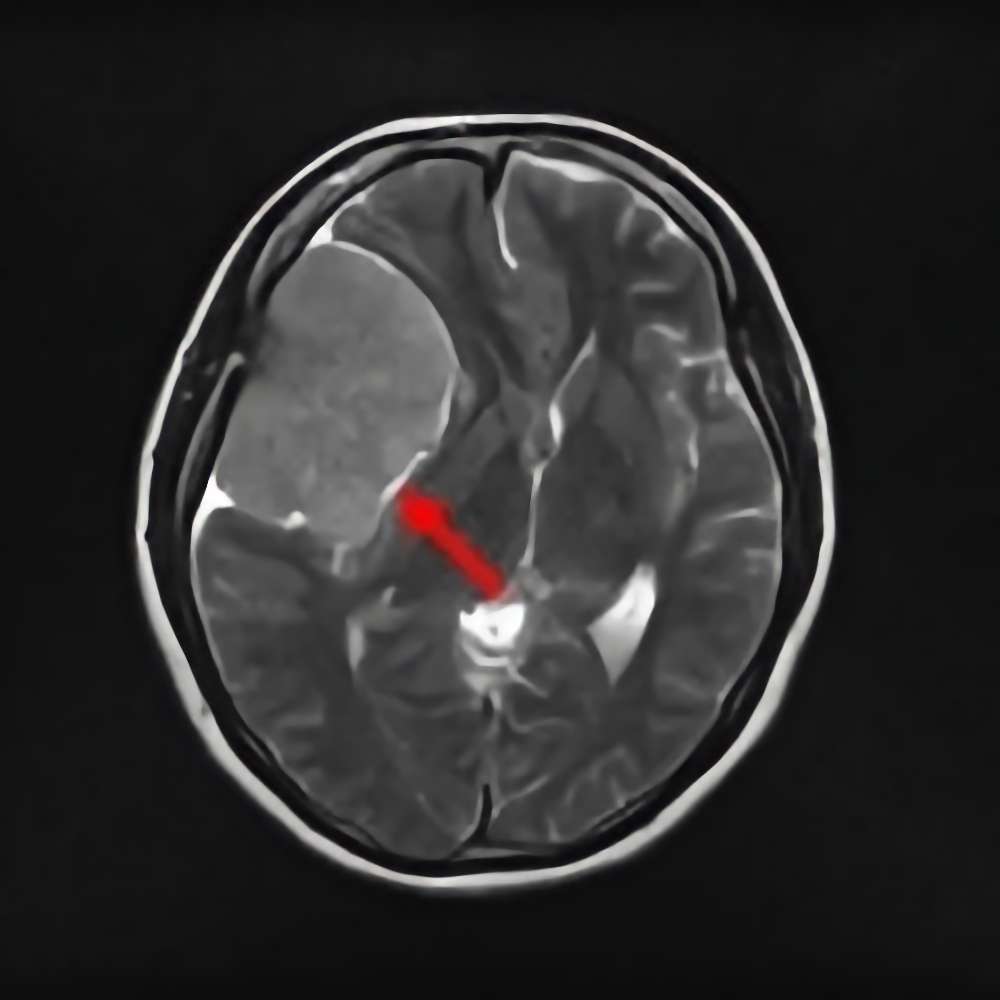

'15年8月

50代

蝶形骨稜髄膜腫

No.’15_108 手術前1

No.’15_108 摘出 前

No.’15_108 摘出 後